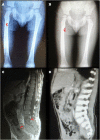

Mutations in the genes coding for cytokines, receptors, second messengers, and transcription factors of interferon gamma (IFN-γ) immunity cause Mendelian susceptibility to mycobacterial disease (MSMD). We report the case of a 7-year-old male patient with partial dominant (PD) IFN-γ receptor 1 deficiency who had suffered from multifocal osteomyelitis attributable to bacille Calmette-Guérin vaccination since the age of 18 months. He developed hemophagocytic lymphohistiocytosis (HLH), a hyper-inflammatory complication, and died with multiorgan dysfunction, despite having been diagnosed and treated relatively early. Patients with PD IFN-γR1 deficiency usually have good prognosis and might respond to human recombinant subcutaneous IFN-γ. Several monogenic congenital defects have been linked to HLH, a catastrophic "cytokine storm" that is usually ascribed to lymphocyte dysfunction and thought to be triggered by interferon gamma. This is the sixth patient with both MSMD and HLH of whom we are aware. The fact that patients with macrophages that cannot respond to IFN-γ still develop HLH, bring these assumptions into question.